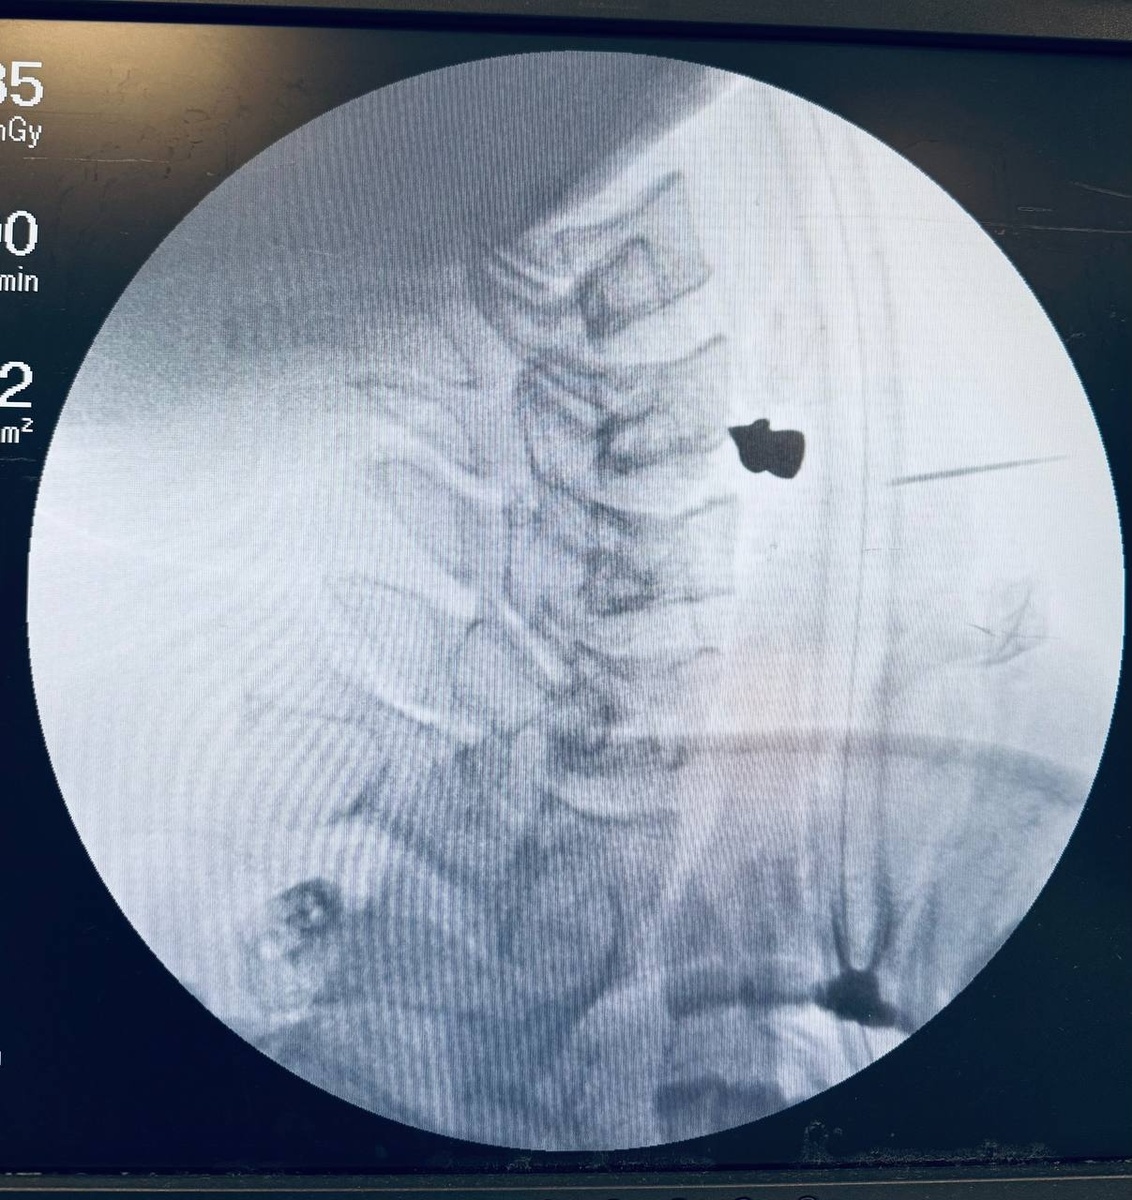

Пуля в позвоночнике: врачи Казани спасли парня, выстрелившего себе в шею из ружья

На момент поступления в РКБ пациенту было трудно глотать и говорить. Компьютерная томография показала, что ни артерии, ни трахея, ни пищевод задеты не были – пуля каким-то чудом прошла через шею и остановилась в позвоночнике. Врачи аккуратно извлекли ее и зашил рану. Вся операция заняла 20 минут. Сейчас пациент восстанавливается, будучи в палате лечебного учреждения.